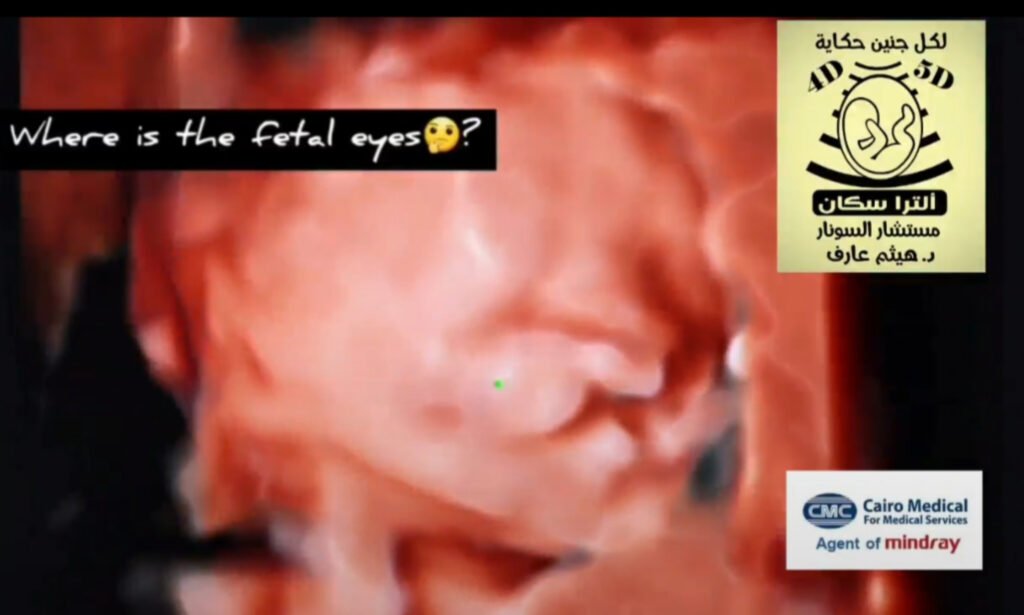

Anophthalmia fetal ultrasound

Prevalence:1 in 20,000 births.Ultrasound diagnosis:In microphthalmia there is decrease in the size of the eyeball and in anophtalmia there is absence of the eyeball, optic nerve and chiasma. Both can be unilateral or bilateral.Associated abnormalities:Chromosomal defects, mainly trisomy 13, are found in >50% of cases.Genetic syndromes are found in >50% of cases. The most common are Goldenhar syndrome (sporadic; anophthalmia, ear defects, facial cleft, facial macrosomia), Fraser syndrome (autosomal recessive; microphthalmia, facial cleft, tracheal atresia, bilateral renal agenesis, heart defects, syndactyly or polydactyly), Fryns syndrome (autosomal recessive; anophthalmia, facial cleft, micrognathia, ventriculomegaly, diaphragmatic hernia).Investigations:Detailed ultrasound examination, including neurosonography.Invasive testing for karyotyping and array.Fetal brain MRI for diagnosis of abnormalities such as absence of the optic nerve.Follow up:Standard follow-up in isolated cases. If there is an underlying syndrome antenatal care should be adjusted according to the risks of the condition.Delivery:Standard obstetric care and delivery.Prognosis:Isolated: good.Syndromic: very poor.Recurrence:Isolated: no increased risk.Part of trisomy 13: 1%.Part of an autosomal recessive condition: 25%.